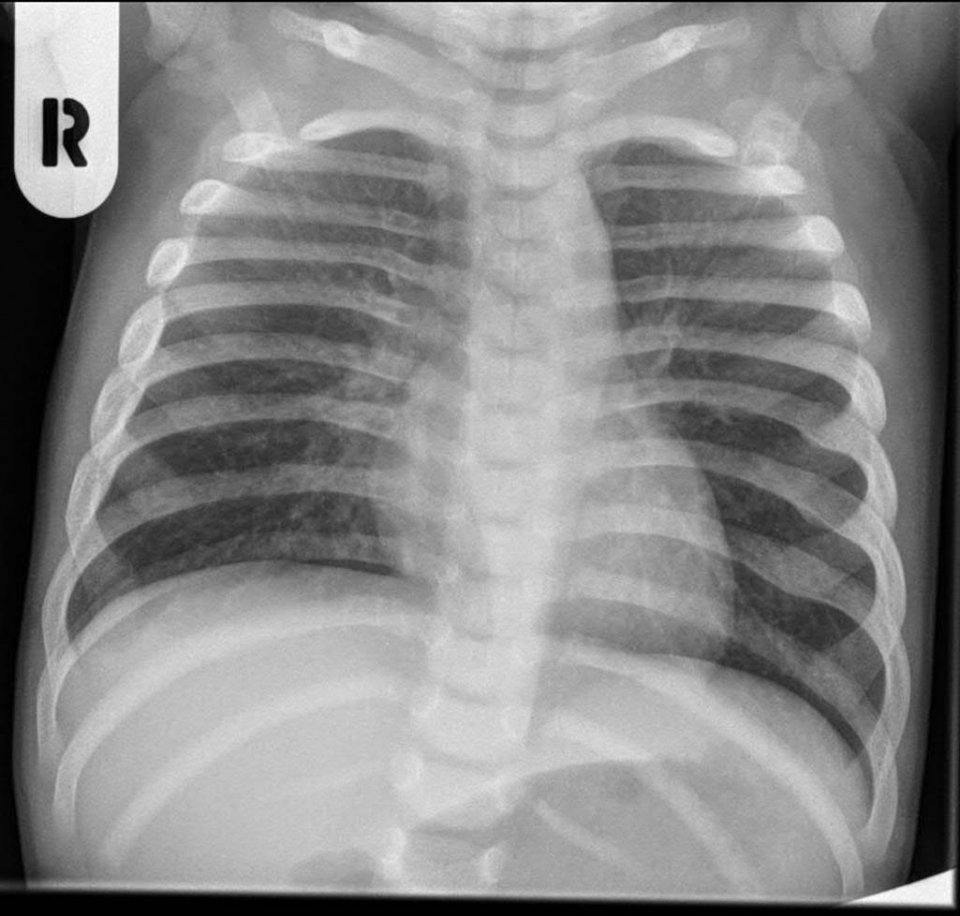

Rippenbruch (Rippenfraktur / Rippenserienfraktur)

Rippenbruch (Rippenfraktur / Rippenserienfraktur). Bist du neugierig, warum Rippenbrüche so schmerzhaft sein können und wie man damit umgehen kann? Auch Monate nach einem Rippenbruch können immer noch Schmerzen auftreten, was an sich nicht ungewöhnlich ist